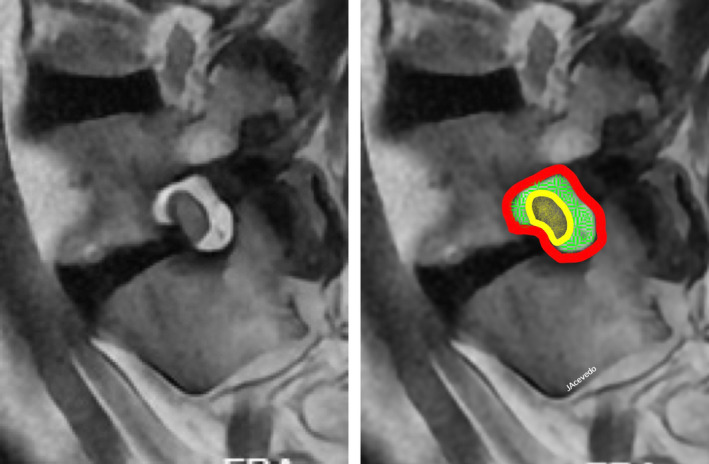

Discussion: Percutaneous procedure targeting the DRG for the treatment of chronic pain requires preoperative planning independent to the study of the etiology of pain. The DRG should be typified using magnetic resonance imaging. We propose a preoperative evaluation scale based on four specific items: A-position in the vertebral canal, B-position of the DRG within the foramen, C-number of ganglia in the root, and D-ratio (proportion) of foramen/DRG.

Abstract Image